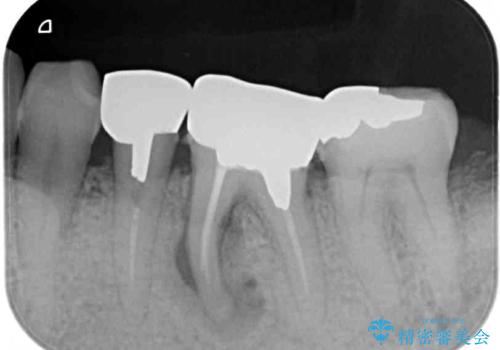

- 上下の奥歯が痛いとのことで来院された患者様です。

診察をしたところ、上下大臼歯の歯肉に排膿路認められたため、根管治療を行い、その後補綴治療を行うこととしました。

治療を開始したところ、上顎は排膿路が消失し、症状も落ち着きましたが、下顎は一向に改善されませんでした。

改めて診療を行ったところ、歯根破折が認められ、抜歯後にインプラント治療を行うこととしました。